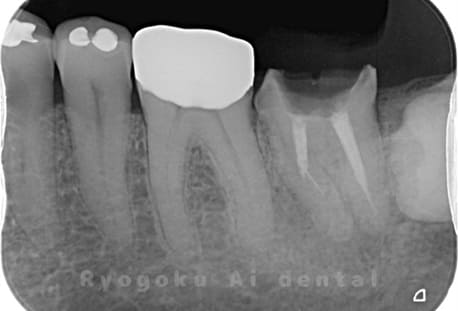

Case05

-

- 原因

- 慢性根尖性歯周炎

- 治療内容

- マイクロエンド

- 治療費用

- 121,000円(被せ物は含まない)

他院ではお薬の交換と抗生剤の処方で経過を診ていた患者さんです。歯茎の腫れが治らないとのことで、根管治療を開始し、2回目のご来院で腫れが引いたケースです。現在は被せ物も入り、良好に経過しております。

<リスク・副作用>

術後は痛み、腫れ、痺れなどの副作用が生じる場合があります。症状が再発する可能性があります。